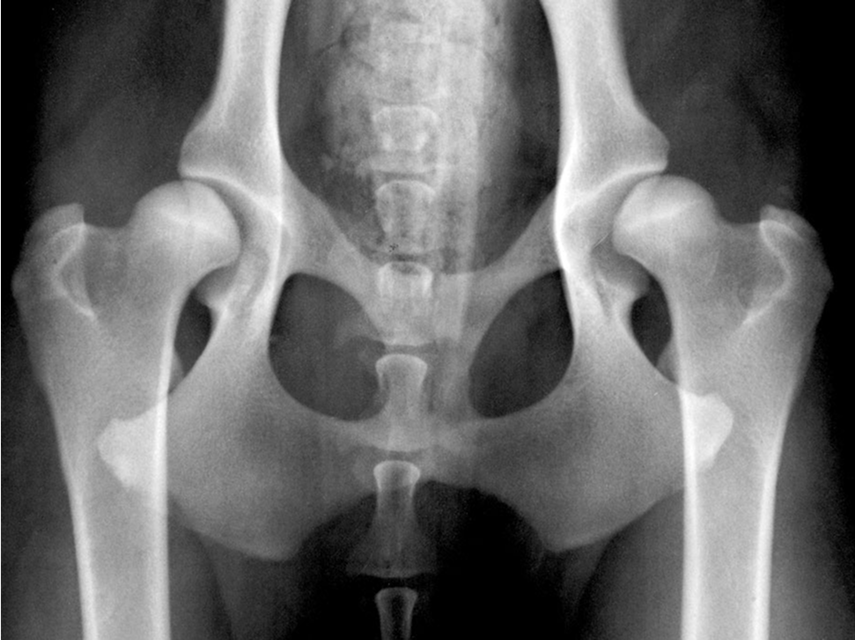

При кормлении растущего щенка сложнее всего определить оптимальное для него количество энергии. Чрезмерное потребление энергии приводит к резкому набору лишнего веса (т. е. темпы роста превышают рекомендуемые), что создает дополнительную нагрузку на растущий скелет (1). Ограничив потребление энергии в фазу роста, можно снизить частоту развития даже некоторых наследственных ортопедических заболеваний, например дисплазии тазобедренного сустава (Рисунок 1) (2). Известно, что у щенков при быстром росте из-за избыточного потребления энергии значительно повышается риск набора лишнего веса и развития ожирения во взрослом возрасте (3). Ежедневные потребности в энергии зависят от ряда факторов: породы, уровня активности, условий содержания, состояния здоровья, поэтому необходимый уровень калорий для разных животных может значительно различаться.